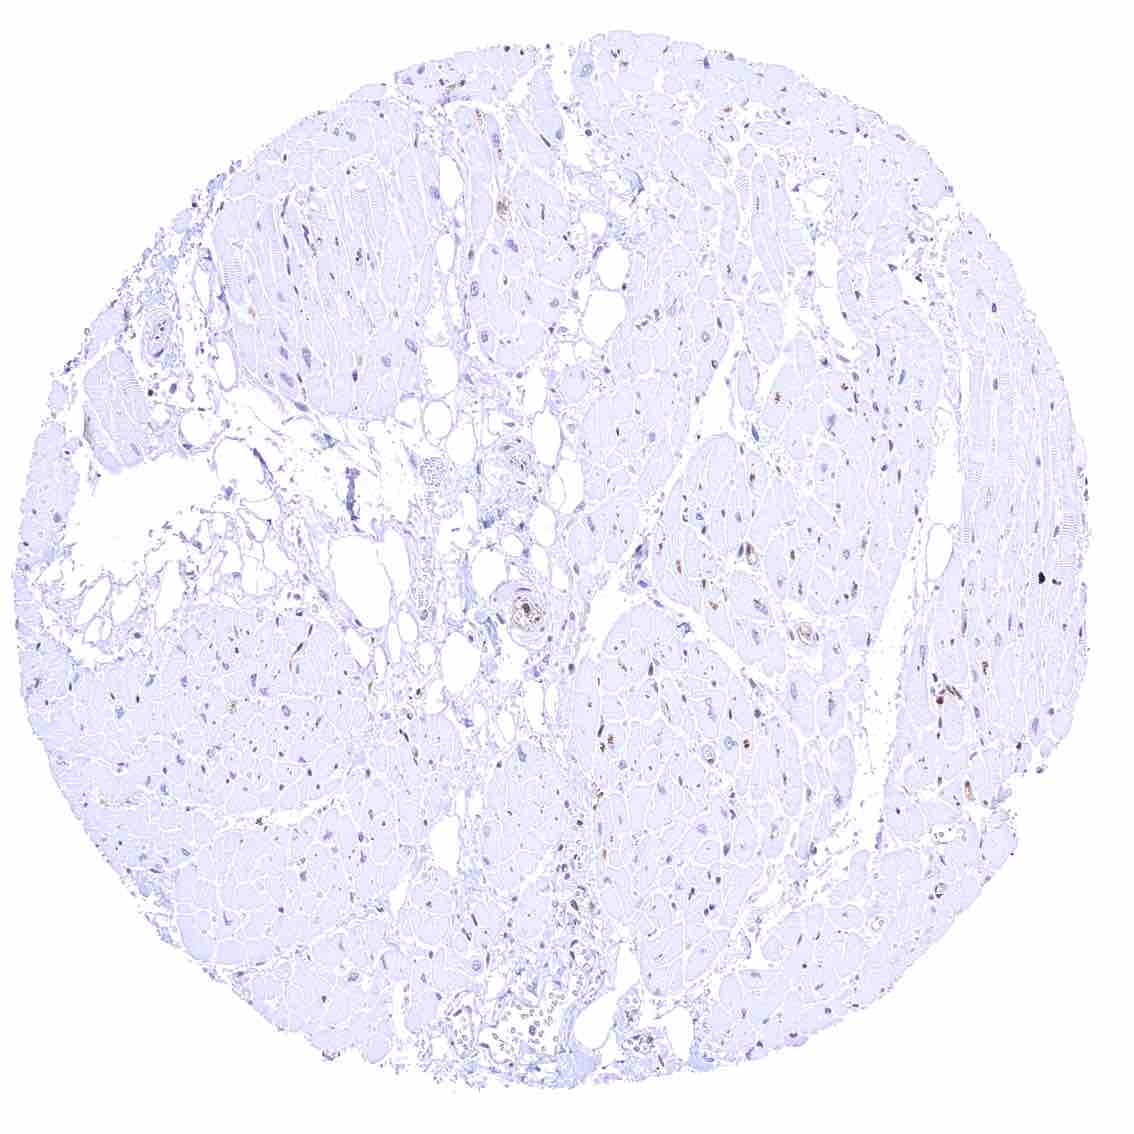

Fat – Variable nuclear p27 staining of at least a fraction of fat cells.

Skeletal muscle – Strong nuclear p27 staining of most but not all cells.